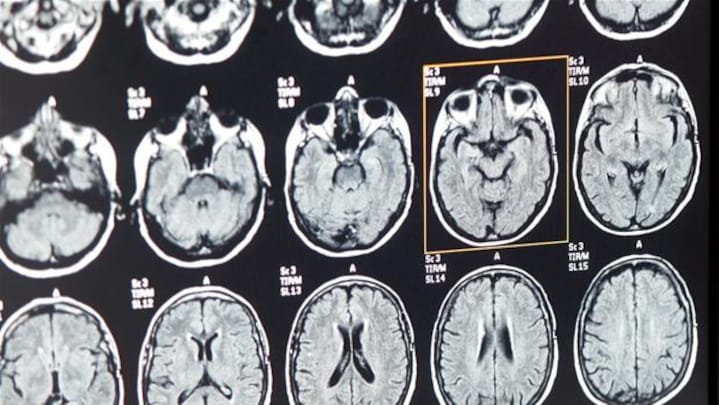

Signalerne fra hjernen blev registreret ved hjælp af implanterede sensorer der på hjernens overflade kunne måle på neuronernes aktivitet med stor nøjagtighed.